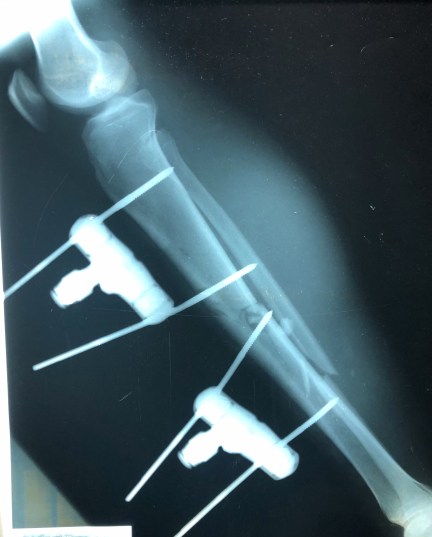

Speaking of Moto accidents. Last week there was a different Moto accident that came in. The accident occurred 8 months prior, and the young man, Buddy (not his real name) had gone to a well known hospital in Tegucigalpa (capital of Honduras). They did an ORIF (where they open the leg, put the bones together, and secure it with pins on the outside of the skin). His post surgery xray is below.

The bones appear to be back in place, although there is some weird pin placement.

Unfortunately, he says at some point things weren’t going well. He says there was ‘damage’ to the skin, and they took him back to surgery. Below is the post-operative x-ray. Does anything seem out of place? Something missing?

Yes, there’s a decent sized chunk of fairly important bone missing. The problem is that the nature of bone isn’t to grow back and bridge that gap. Oopsies… This, my friends, is what many people would call a cluster-doodle. Or something like that…

Buddy went back to the other hospital 5 times trying to get them to fix the leg. They kept putting him off with various excuses. I think I know why…

Our surgeons are left with the very difficult task of trying to redeem this dilemma, and get this fellow walking again. It’s not so simple as just putting a place holder in there. I know they are consulting orthopedic specialists back in the States, deciding upon the best course of action.